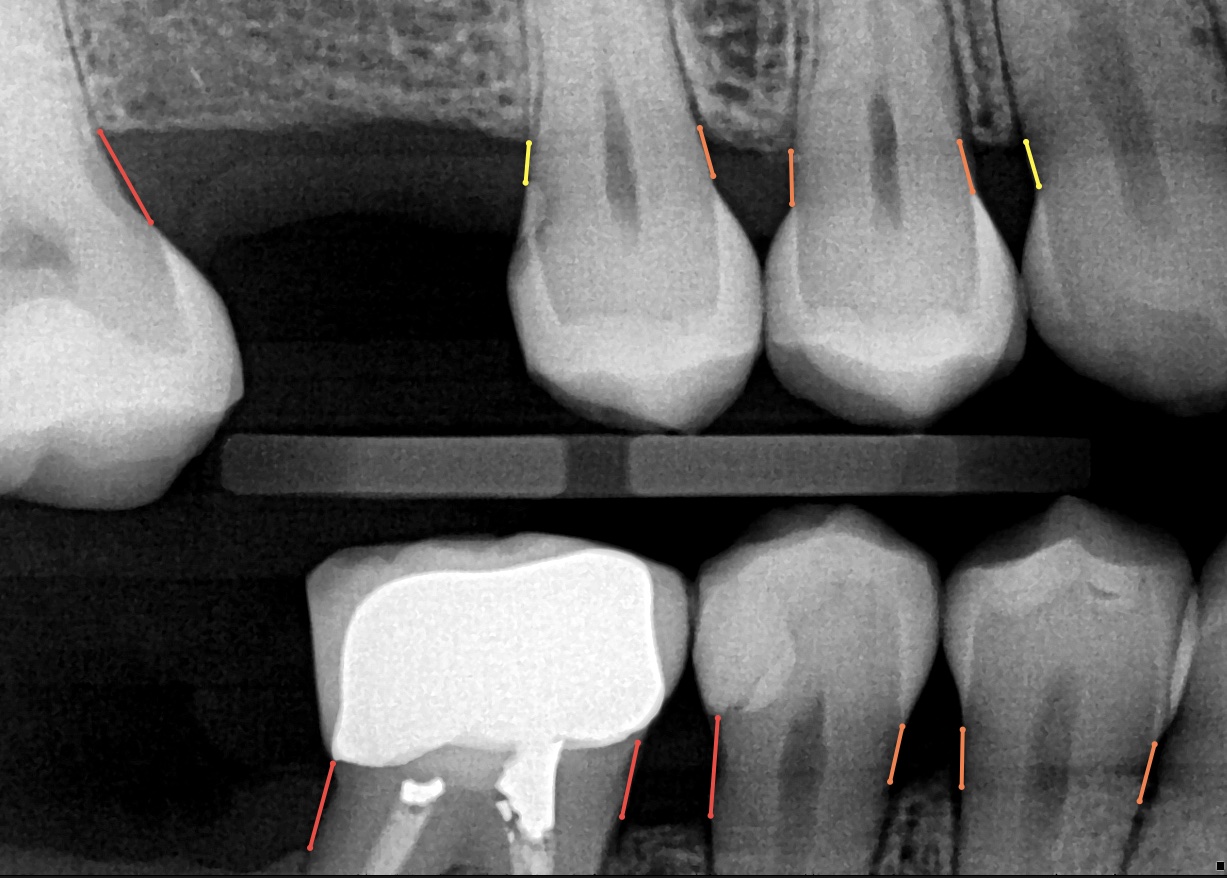

The startup, co-founded by dentist-turned-entrepreneur Dr. Hamed Fesharaki, Yasaman Nemat, PhD, and Shifeng Chen, has just cleared FDA approval for its first AI-driven product, Adravision Perio, that helps dentists and dental hygienists measure bone levels on dental radiographs during an appointment. For busy dentists, the tool can streamline the identification and prevention of gum disease.

Adravision’s Perio software can play an important role in “diagnosing and planning treatments for periodontal disease,” she added. That is particularly important as periodontal disease (gum disease) affects up to 90% of the population.

“In the United States, cross-sectional studies indicate that approximately 50% of adults currently grapple with some form of gingivitis, the initial stage of gum disease. Left unaddressed, gingivitis can progress to periodontitis, posing risks of tooth loss and discomfort during chewing. Adravision's AI-driven solution can help dentists and hygienists more effectively identify signs of periodontal disease and clearly communicate findings with patients in a highly engaging and visual presentation format. Adravision Perio also employs interactive and engaging tool to help dentists and hygienists to better explain problems to their patients which results in more quality and timely care.”

After just two years into operations, Adravision recently secured its initial FDA clearance after displaying that its “automated bone level measurement capabilities [were] akin to a proficient team of dentists,” added Nemat.